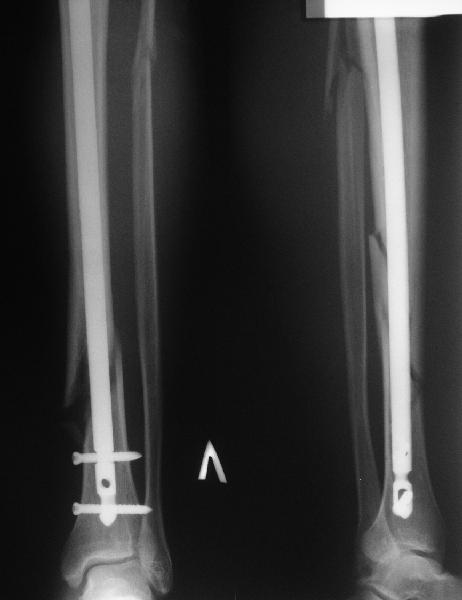

Стержень с большим диаметром и подлиннее?

С ходу не могу понять, почему неправильно фиксирован перелом.

Внизу стержень всего один статический винт держит?

Вальгус, стержень в дистальный отломок введен не на оптимальную длину. Такой диастаз будет долго заполняться, что чревато переломом стержня по ближайшему отверстию.

Вальгус сам по себе небольшой. Имеется промежуточный отломок, который не притянулся, так как отломки до конца не растянули. Сейчас наверное стоит подождать 2-3 мес. и посмотреть как пойдет срастание.

На снимке сохранен небольшой вальгус, но имеется нормальная аппозиция медиального кортикального слоя и поэтому трудно согласится что здесь имеется неправильно фиксированный перелом. Для идеального сопоставления таких косых переломов надо открывать фокус травмы, но тогда меняется философия фиксации.